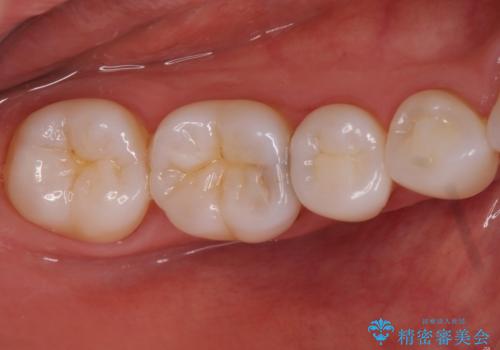

奥歯の虫歯 セラミックインレーでの治療

- 奥歯の黒ずみが気になるとのことで来院されました。

検査の結果、歯と歯の間に小さな虫歯ができていることが確認できました。

白い詰め物をご希望されたため、今回はセラミックインレーでの治療となりました。

黒ずみもなくなり、虫歯も取り切ることができ大変満足していただけました。

虫歯の除去後に適合の良い修復物を装着することは今後の虫歯リスクを減らすことに繋がります。